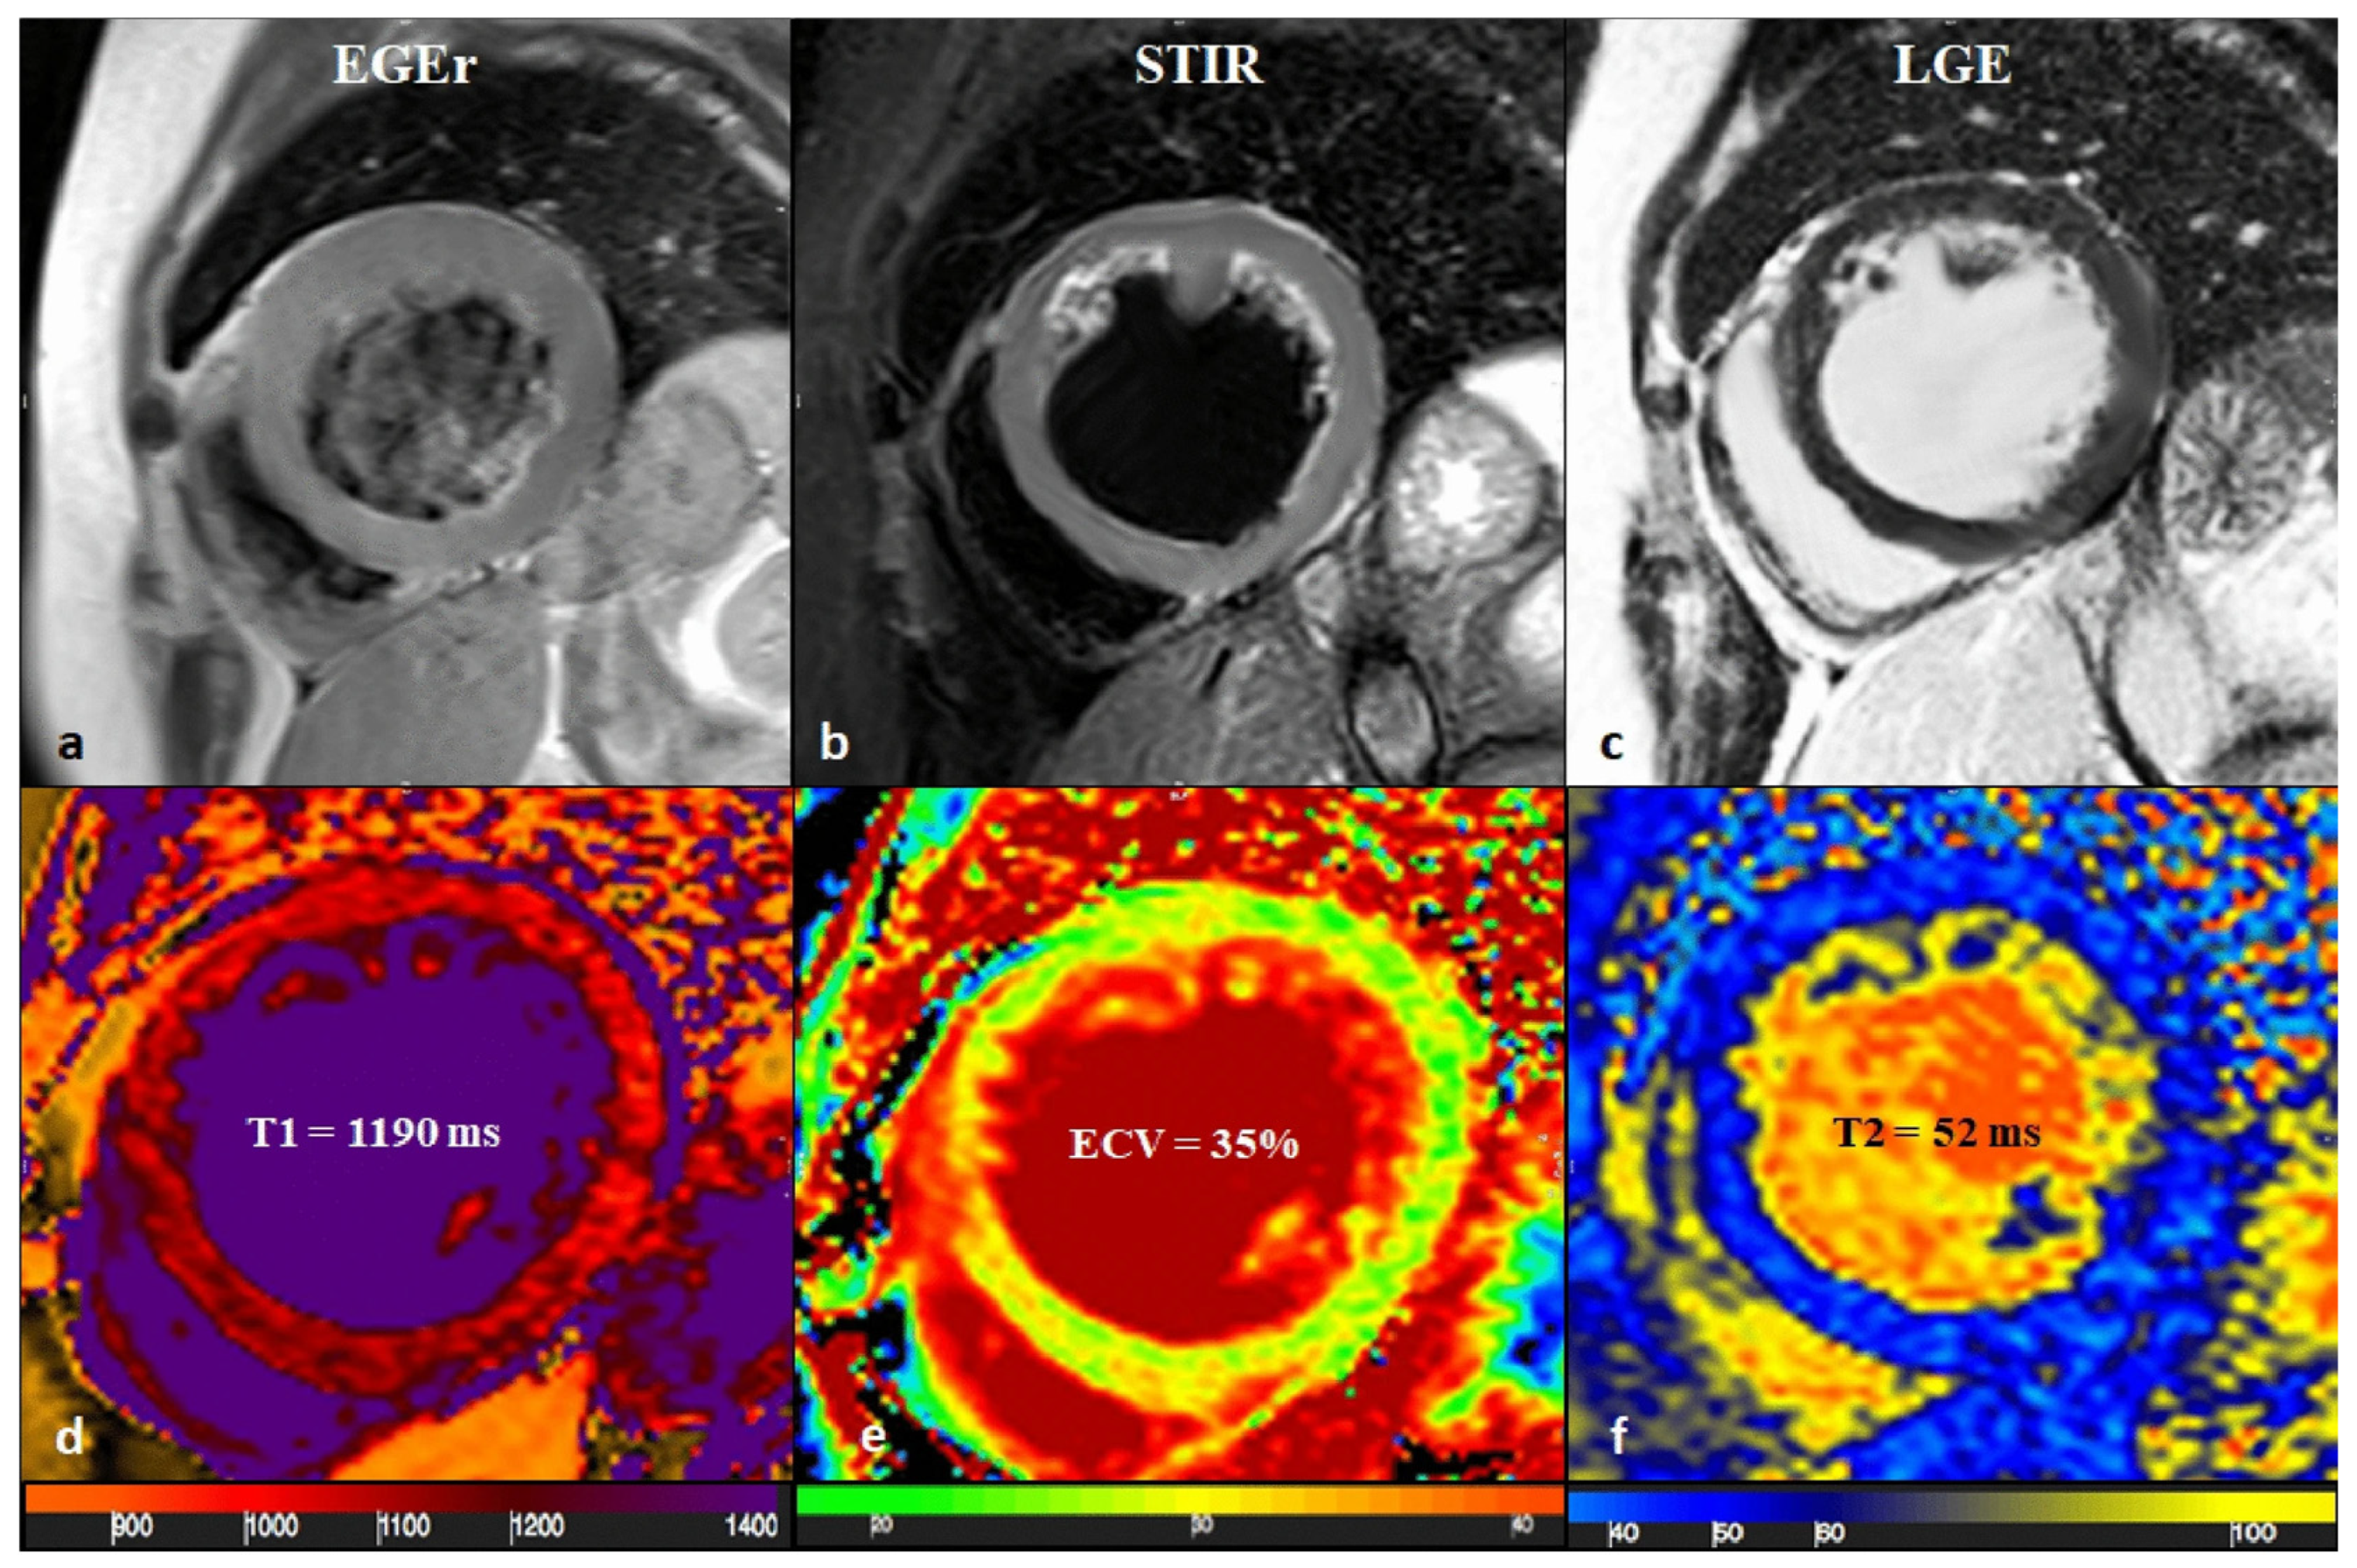

CMR findings and differentiating features are as follows (Figure 8):

Figure 8.

CMR frames of a patient with biventricular ACM. Morpho-functional abnormalities of the RV can be appreciated on a 4-chamber view (A) and right ventricular 2-chamber long-axis view (B) of cine images, evidencing RV dilatation (A, double-head arrow) and multiple sacculations of the inferior and RVOT regions (B, arrows). Structural alterations of the LV are showed in a 4-chamber view (C, arrowhead) and short-axis view (D, arrowhead) of T1-weighted images, where fibro-fatty infiltration of the infero-lateral LV walls becomes evident as a hyperintense signal with a typical bite-like pattern. ACM, arrhythmogenic cardiomyopathy; LV, left ventricle; RV, right ventricle; RVOT, right ventricle outflow tract. Reproduced from: Cipriani, A., et al. (2023) [39]. Licensed under CC BY 4.0 (https://creativecommons.org/licenses/by/4.0/ accessed on 15 December 2025).

- LGE Pattern: The LGE in ACM is typically subepicardial or mid-myocardial, with a predilection for the basal and mid-cavity segments of the LV inferolateral wall. This pattern significantly overlaps with viral myocarditis [39].

- RV Involvement: A key differentiator is concomitant RV structural abnormality. Findings include RV dilation, systolic dysfunction (reduced RV ejection fraction), and LGE or fat infiltration in the RV free wall. However, in left-dominant ACM, RV changes can be subtle or absent.

- Regional Wall Motion Abnormalities (RWMAs): Cine imaging may show regional hypokinesia or akinesia in the LV inferolateral wall or RV, which can also be seen in myocarditis.

Given the overlap, a family history of sudden cardiac death or ACM, and the presence of characteristic ECG findings (e.g., T-wave inversions in right precordial leads or inferior/lateral leads, albeit non-specific) are crucial clues. The 2023 ESC Cardiomyopathy guidelines emphasize that in cases of suspected myocarditis with an atypical or recurrent course, the diagnosis of ACM should be considered, and genetic testing for desmosomal mutations (e.g., PKP2, DSP, and DSG2) is recommended [42]. A pathogenic variant confirms the diagnosis and enables cascade screening of family members.